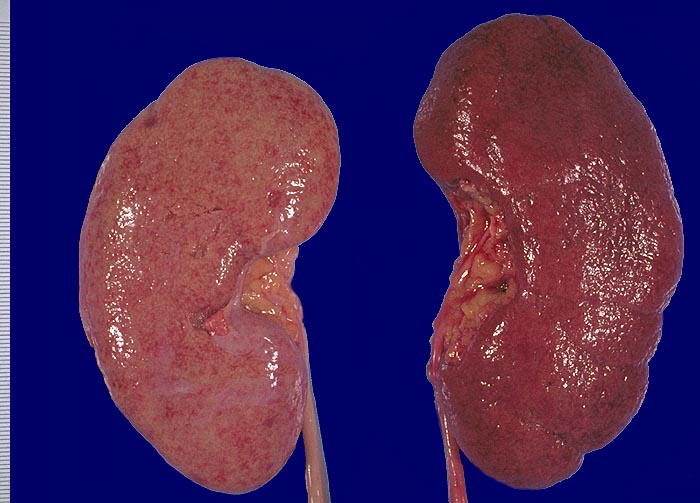

Im allgemeinen ist die Niere infolge von Glomerulumhypertrophie und Tubulushyperplasie vergrössert und derb, die Oberfläche ist granuliert. Bei schwerer Atherosklerose und fortgeschrittener Niereninsuffizienz kann die Niere auch normal gross oder verkleinert sein. Die Kombination von nodulärer Glomerulosklerose, hyalinen Schlingenkappen (=Proteinthromben in den Glomerulumschlingen (> 1916)) oder Kapseltropfen (> 1907) und Arteriolosklerose in Vas afferens und efferens ist beweisend für eine diabetische Nephropathie. Jede einzelne Läsion für sich genommen ist aber unspezifisch. Eine noduläre Glomerulosklerose kann auch vorkommen bei membranoproliferativer Glomerulonephritis (> 2652), Leichtkettenglomerulopathie oder Amyloidose (> 2019). Der nodulären Glomerulosklerose geht bei Diabetikern eine diffuse Glomerulosklerose (> 1906) voraus. Dabei zeigen die glomerulären Basalmembranen und das Mesangium eine progrediente gleichförmige Verbreiterung. Bei der nodulären und diffusen Glomerulosklerose handelt es sich aber wahrscheinlich um zwei pathogenetisch unterschiedliche, sich überlagernde Krankheitsbilder. Typisch bei Diabetikern ist im Unterschied zur arteriellen Hypertonie die Arteriolosklerose von Vas afferens und efferens (> 1911) und oft auch der Vasa recta. Intrarenale Arterien können eine Atherosklerose mit Atheromen zeigen. Subendotheliale Proteinablagerungen teilweise mit Verschluss der Glomerulumschlingen (Schlingenkappen) und knotige Proteinablagerungen in der Bowman'schen Kapselbasalmebran (Kapseltropfen) gehören zu den sogenannten exsudativen Läsionen (> 1919) (> 1920) der diabetischen Nephropathie und führen zu Synechien sowie zur globalen Glomerulosklerose. Gleichzeitig mit den Glomerulumveränderungen treten tubuläre Basalmembranverbreiterungen auf, später eine Tubulusatrophie und interstitielle Fibrose mit Begleitentzündung. Auch die Basalmembranen der peritubulären Kapillaren sind verdickt.

Makroskopie

Befund

Pathologischer Befund